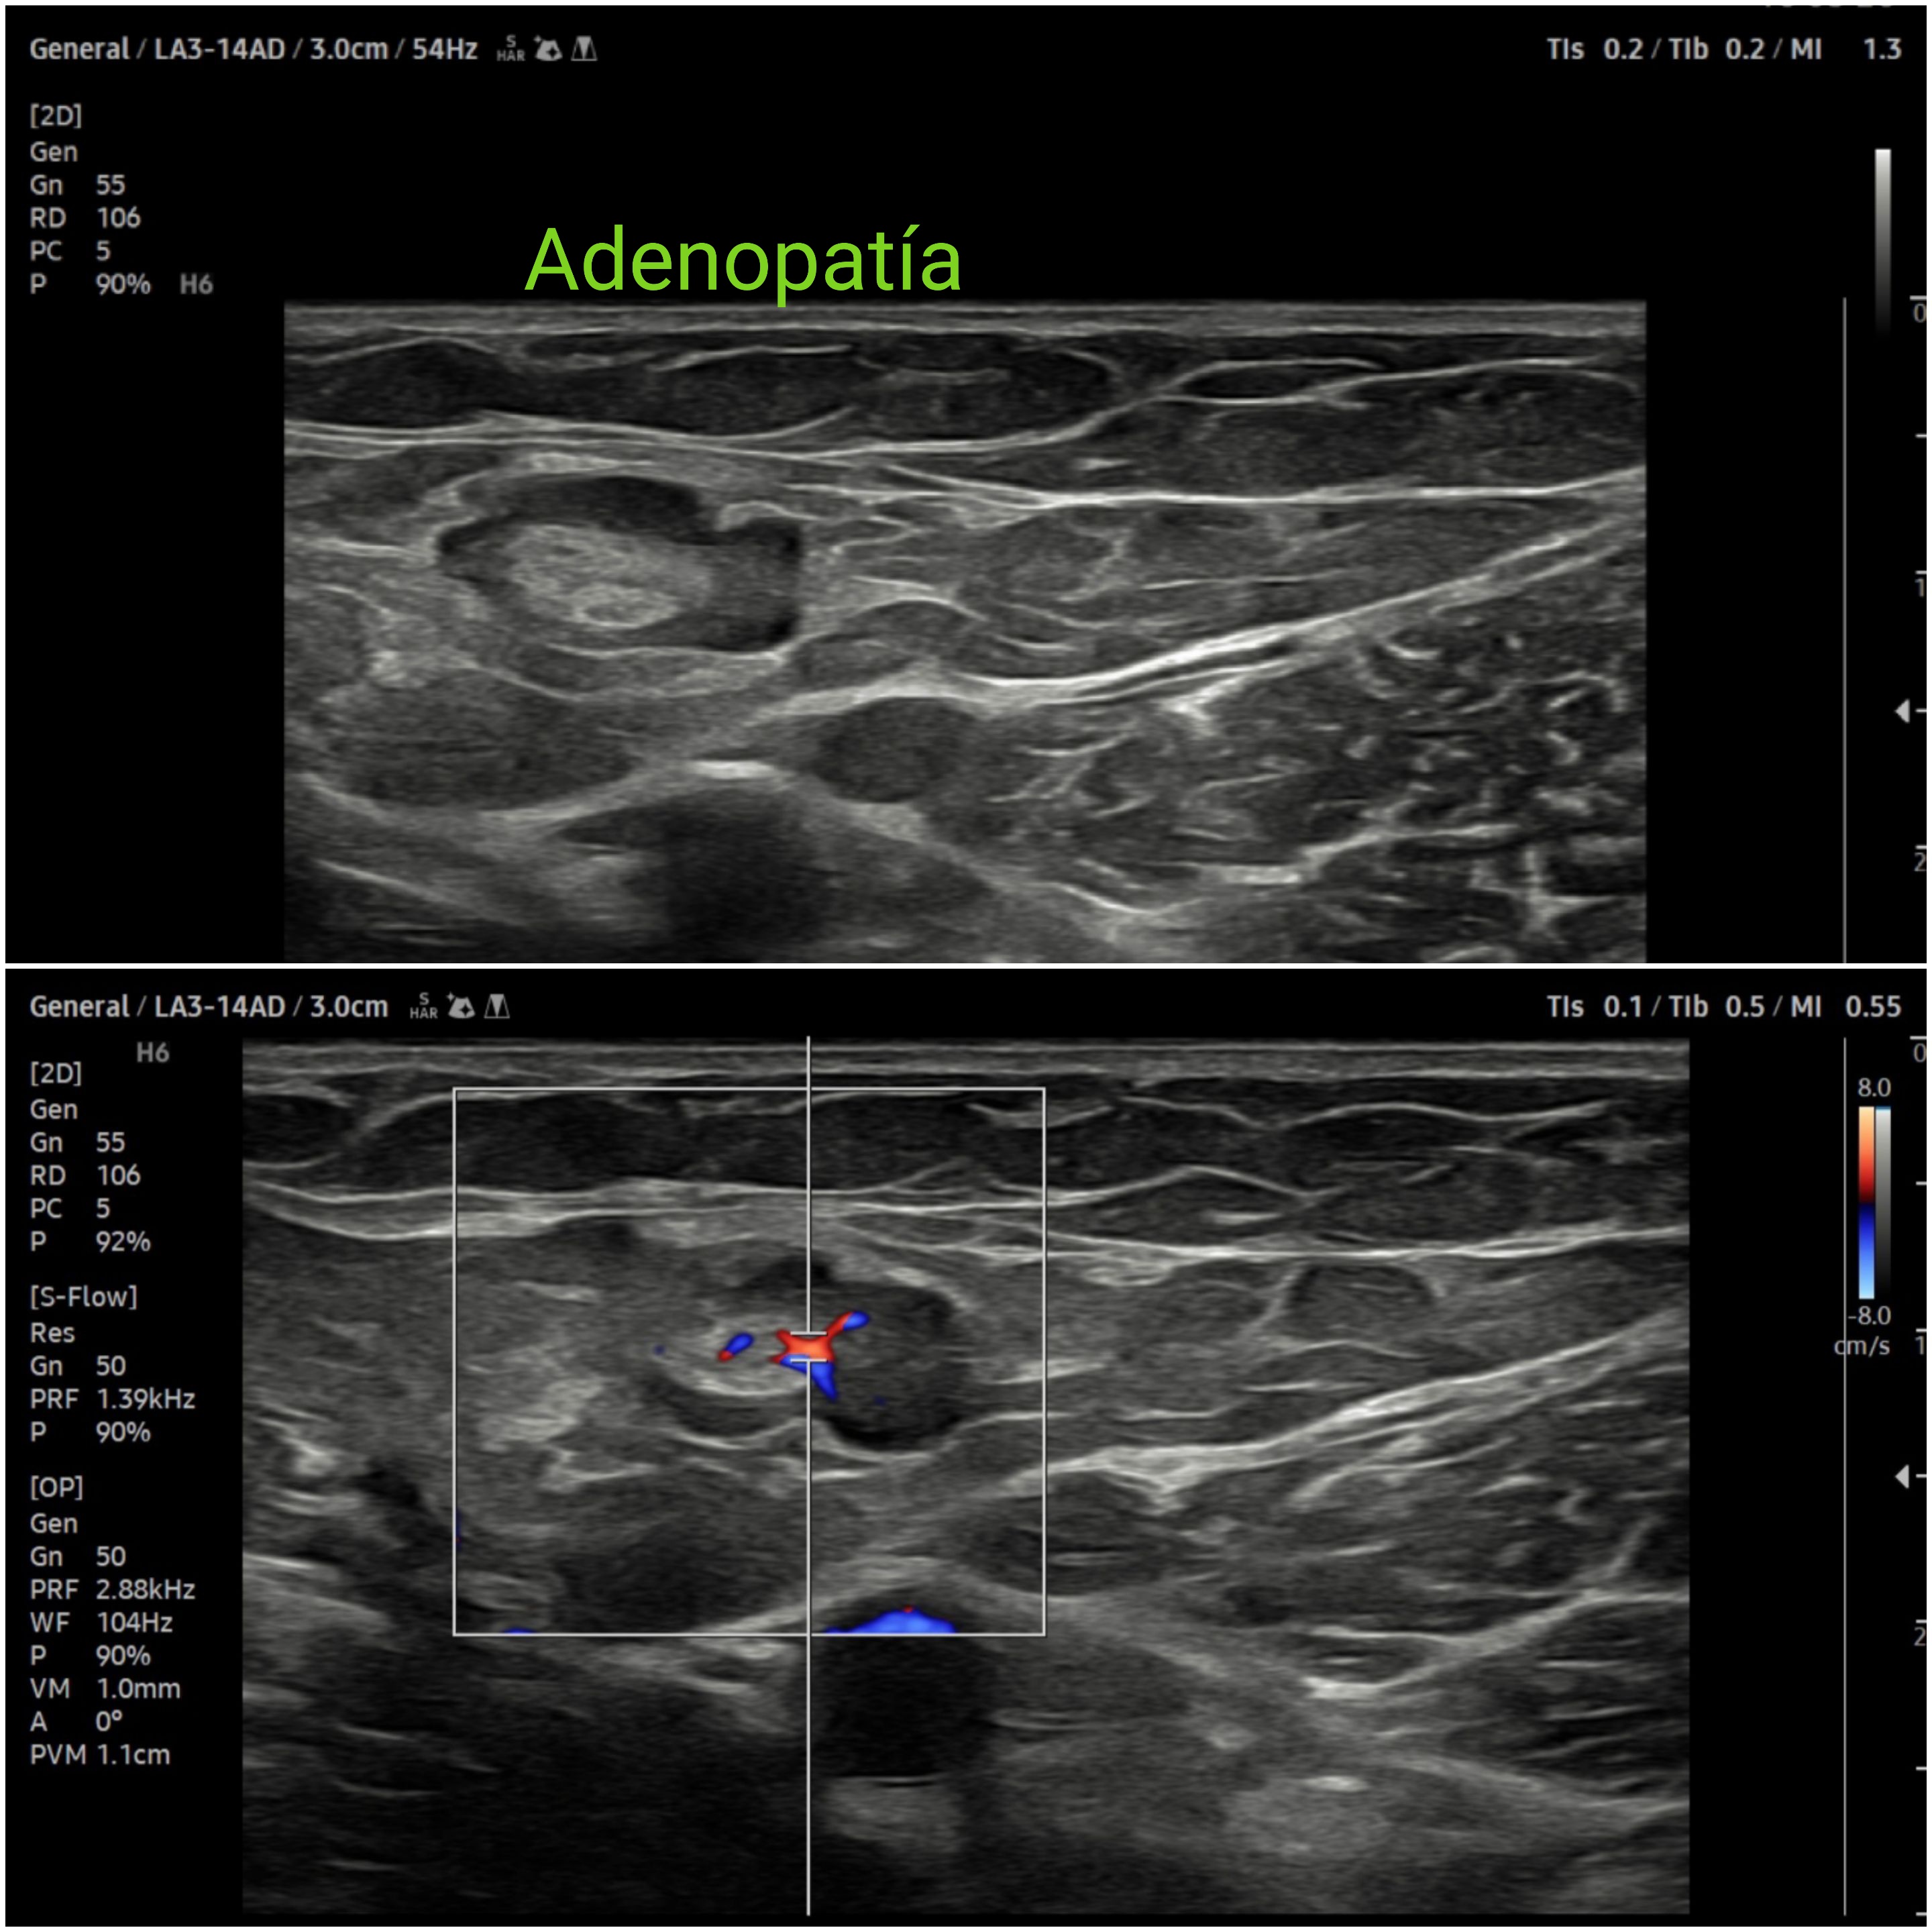

Dolor inguinal.

Presentación de 8 casos clínicos que consultan por dolor inguinal. Si bién cada caso tiene matices clínicos y de exploración, desde el punto de vista docente compatir lo que aportan los diferentes hallazgos ecográficos al siempre desafiante dolor inguinal.

Hallazgos ecográficos

En caso de hernias inguinales se remite a cirugía; por patología coxofemoral derivación a Traumatología descartada la patología muscular. Tratamiento conservador la tendinopatía del psoas. Derivada a urgencias, confirmada la sinfisitis pubis y la trombosis venosa con buena evolución posterior. Y seguimiento en la adenopatía.

La ecografía clínica, aplicada de forma sistemática con maniobras dinámicas, complementa el abordaje del dolor inguinal reduciendo la incertidumbre, la demora diagnóstica y permite orientar mejor dicha patología así como descartar patología escrotal o trombosis venosa.